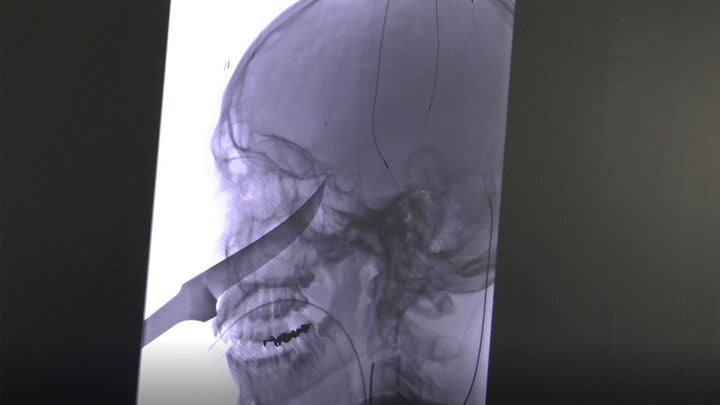

Apparently, Eli was handling the knife when he fell and it went through his face, becoming embedded in his skull. The tip of the blade stopped right at his carotid artery.

A slight cut or tear would have led to massive bleeding, so Ebersole and his team had to control the blood supply to the area with balloons and catheters before they could actually remove the blade from Gregg’s face, according to Fox News.

The surgeons reported that they had to use a vise to grip it, rather than their hands.